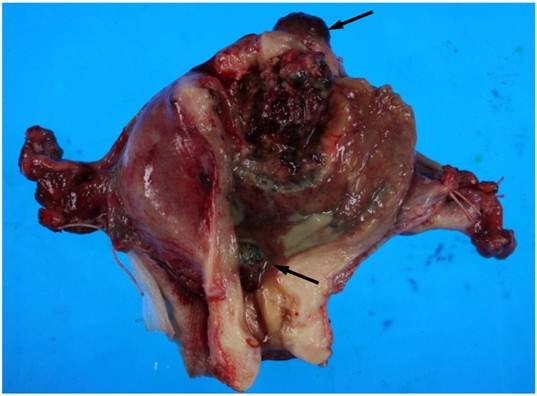

On macroscopic examination of the uterine specimen, a huge ulceroinfiltrative necrotic mass was located on the posterior wall, and a hemorrhagic nodule was located in the serosa of the uterine fundus and internal cervical os (Figure 1).

Gross findings of the uterus. A huge ulceroinfiltrative necrotic mass measuring 40 × 40 mm is located on the posterior wall and a diffuse dark reddish hemorrhagic nodule (arrows) is located in the serosa of the uterine fundus and internal cervical os.